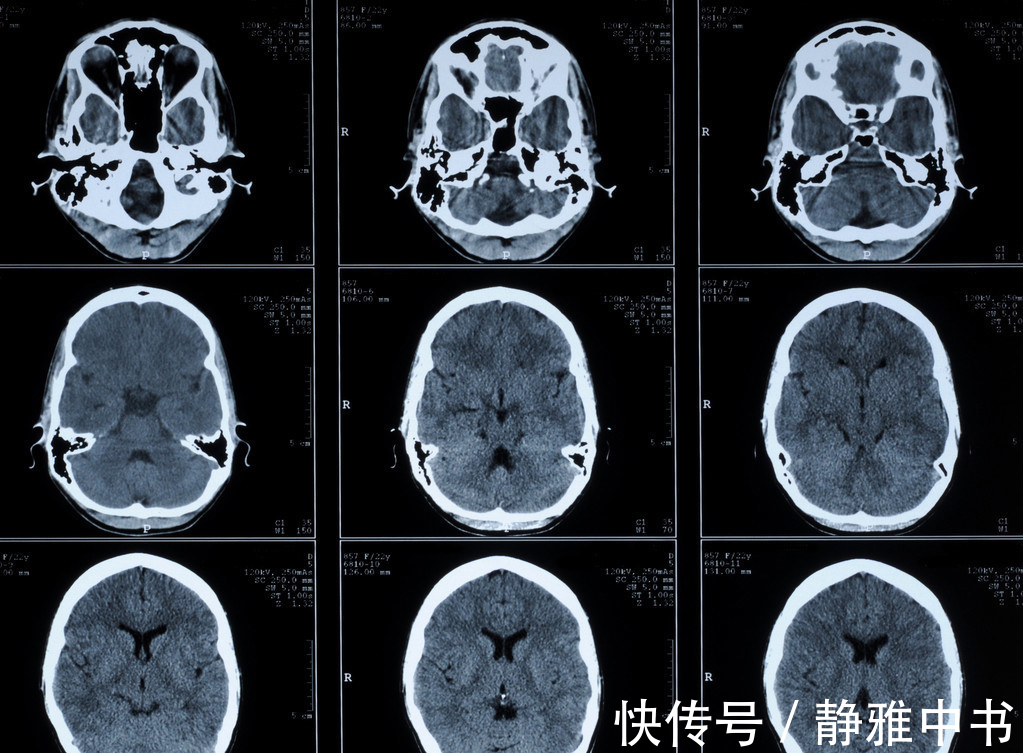

1.脑CTA 即脑CT血管造影,属于非创伤性血管成像技术,颅脑CTA就是给被检查者的静脉中快速注入碘造影剂,通过血液循环然后进行CT检查,经计算机对图像进行处理后,可以三维显示颅内血管系统,CTA可清楚显示大脑动脉环(Willis环),以及大脑前、中、后动脉及其主要分支,对闭塞性血管病变可提供重要的诊断依据。可以将缺血性脑血管病的诊断提早到发病后2小时。